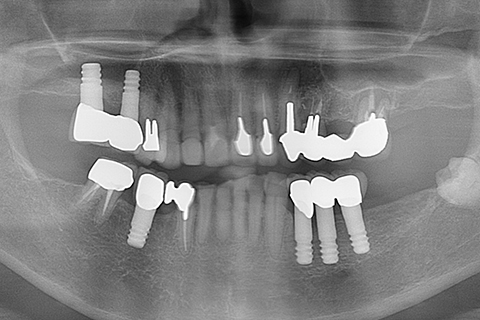

症例1

- 年齢・性別

- 55歳女性

- 治療期間

- 2ヶ月

- 抜歯

- なし

- 治療費

- 66万円

- 備考

- 右下6.7欠損

- 治療内容

- 右下6.7欠損部にインプラント埋入

- 施術の副作用(リスク)

- オペによる知覚障害。インプラントによる歯肉炎。インプラント脱落。